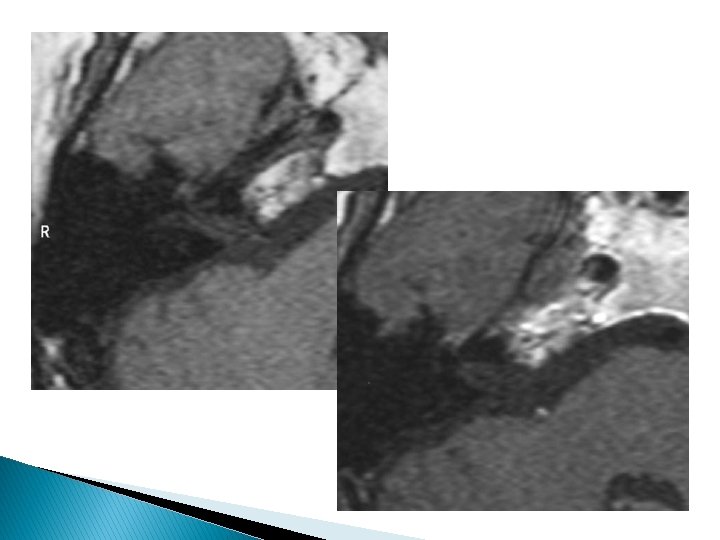

Hémangiome � Ganglion géniculé +++ � Hypersignal � Prise T 2 de contraste intense, progressive

� Lyse périlésionnelle � calcifications TDM